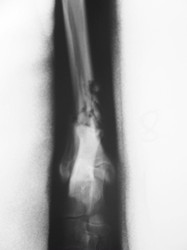

Fijación Externa

PRÁCTICAS CURSO DE FIJACIÓN EXTERNA PERFECCIONAMIENTO.

Híbrido.